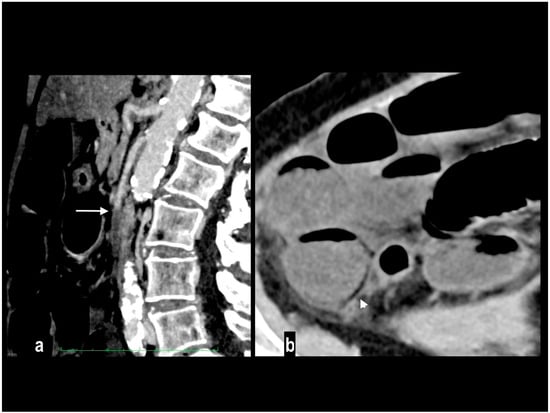

An uncommon cause of arterial thrombosis is SMA dissection, which can occur as a continuation of aortic dissection or in isolation [49]; spontaneous isolated superior mesenteric artery dissection is defined as superior mesenteric artery (SMA) dissection without the presence of aortic dissection [50]. SMA spontaneous dissection is a rare cause of mesenteric ischemia (<5%) in males between the fourth and the fifth decade with no particular medical history [17], and typically affects the convex surface of the SMA trunk, at a distance of 1 to 3 cm away from the root [51]. Many classifications have been proposed for SMA dissection [50,52,53,54] to determine the shape, location, and extent of the false lumen, and whether the false lumen is thrombosed or the true lumen is stenotic. SMA dissection is responsible for acute pain and may or may not determine intestinal ischemia. Mesenteric ischemia in SMA dissection occurs when critical luminal stenosis or occlusion by false lumen thrombosis determines vessel occlusion and consequent bowel involvement [50]. The CT findings of SMA dissection are focal dilation, intimal flap, intramural hematoma, false lumen thrombosis, increased fat attenuation around the SMA, and mesenteric hematoma (Figure 5) [55,56]. Rarely, large vessels mesenteric arteritis can develop mesenteric ischemia as a devastating complication when parietal inflammation produces critical luminal stenosis or occlusion, presenting acutely and often requiring resection [57].

Figure 5.

SMA dissection in a 42-year-old woman. MIP arterial images (a,b) showed segmentary false lumen thrombosis in the proximal convex side of SMA, with lumen narrowing (arrow). The vessel caliber had increased ((c) oval). Distally, the intimal flap continued in a complete vessel thrombosis (arrowhead), determining bowel ischemia with hypoenhancing paper-thin bowel walls (d). Proximal false lumen thrombosis (arrow) and intimal flap (arrowhead) were also well depicted at ultrasound examination performed before MDCT (e,f). The patient underwent surgical resection of necrotic loops.